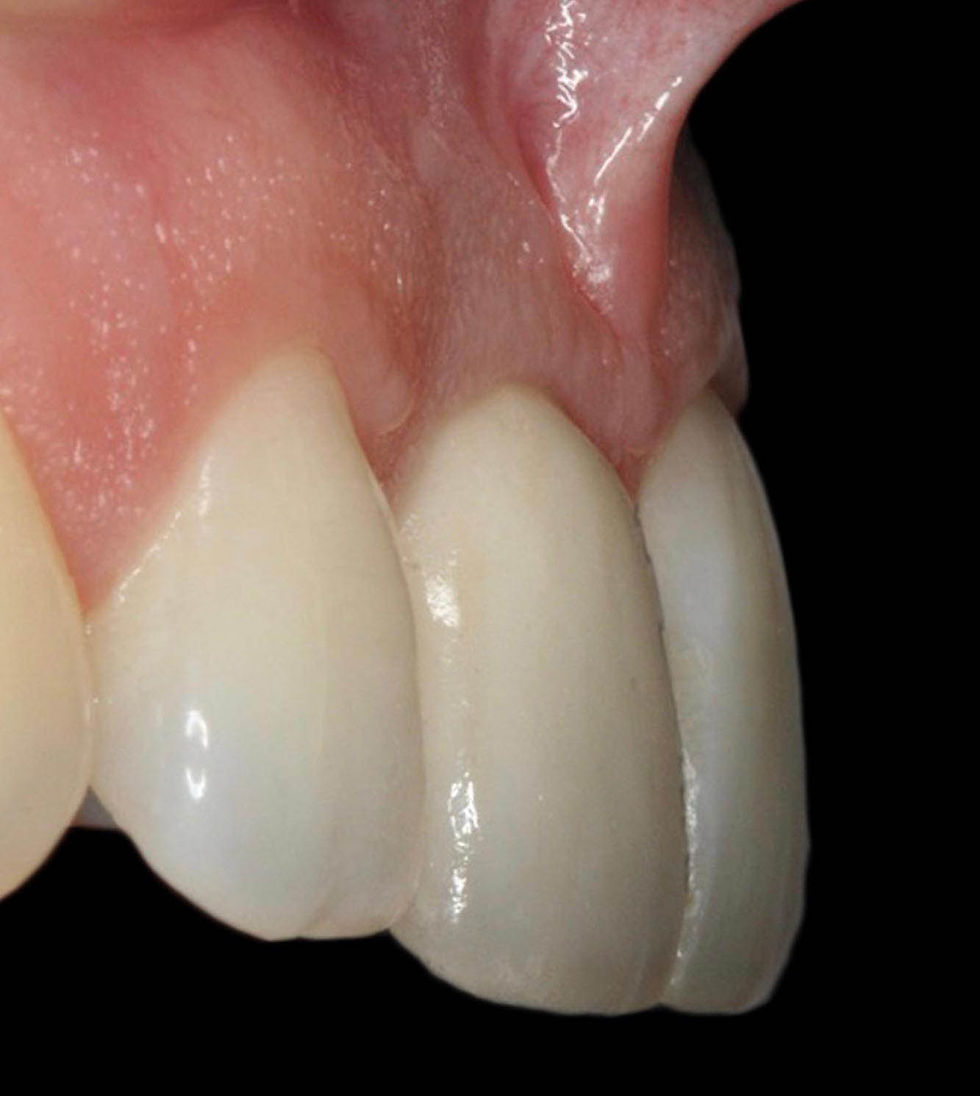

Lateral view that shows the good condition of the vestibular soft tissues and their thickening over time.